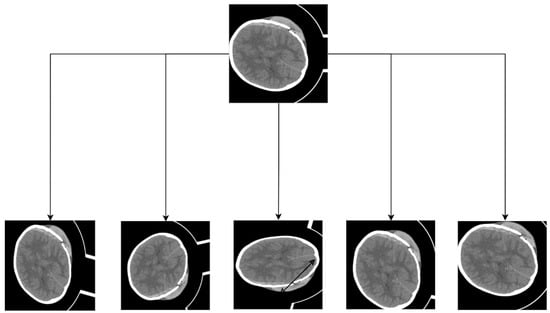

3.1. Image Preprocessing